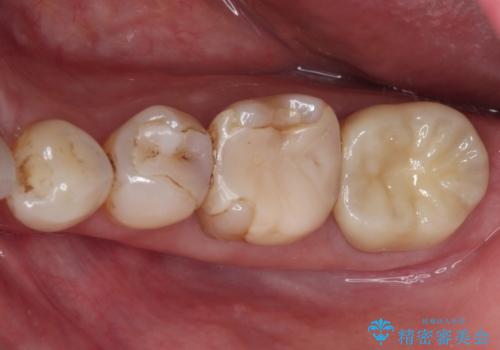

- 近医にて奥歯の抜歯が必要と言われたとのことで来院された患者様です。

診査の結果、歯が破折しており、抜歯が必要な状態でした。

最後方歯であるため、入れ歯かインプラントかどちらかの補綴治療を行うこととなりますが、ご希望によりインプラント補綴治療を行うこととしました。

インプラントにはストローマン社のSLActiveを使用し、埋入から補綴までおよそ3か月と、短期間で治療を進めることができました。